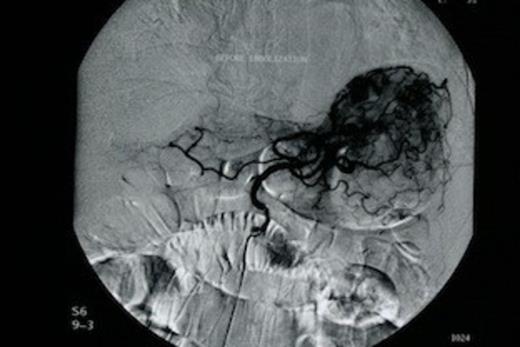

The patient was subjected to emergency oesophago-gastroduodenoscopy, which revealed extensive angiodysplasia of the gastric body. At first, conservative management was attempted with intravenous fluids and transfusions. After initial stabilization of the patient (Ht: 32.5%, 90bpm, 110/50mmHg), rebleeding was encountered within 48 hours and therefore decision for interventional radiology, embolization of the angiodysplasia, was made. Urgent angiography of the left gastric artery revealed extravasation of contrast material from the gastric body (Figure 1). Following that, successful arterial coil embolization, using super selective catheterization was achieved in the distal and proximal parts of the ruptured vessel (Figure 2). Consequently the patient recovered from the hemorrhagic shock.

Urgent angiography of the left gastric artery revealed extravasation of contrast material from the gastric body

Successful arterial coil embolization, using super selective catheterization in the distal and proximal parts of the ruptured vessel